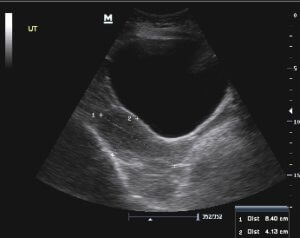

УЗД діагностика

- ультразвукове обстеження сечового міхура

Діагностика може здійснювати як безпосередньо для підтвердження діагнозу, так і виявлення точного характеру захворювання, що впливає на спосіб лікування. Наприклад, ультразвукове дослідження дозволяє визначити форму променевого циститу за рахунок вивчення патологічних змін сечового міхура, які візуально помітні при виразковій або судинної різновиди хвороби.